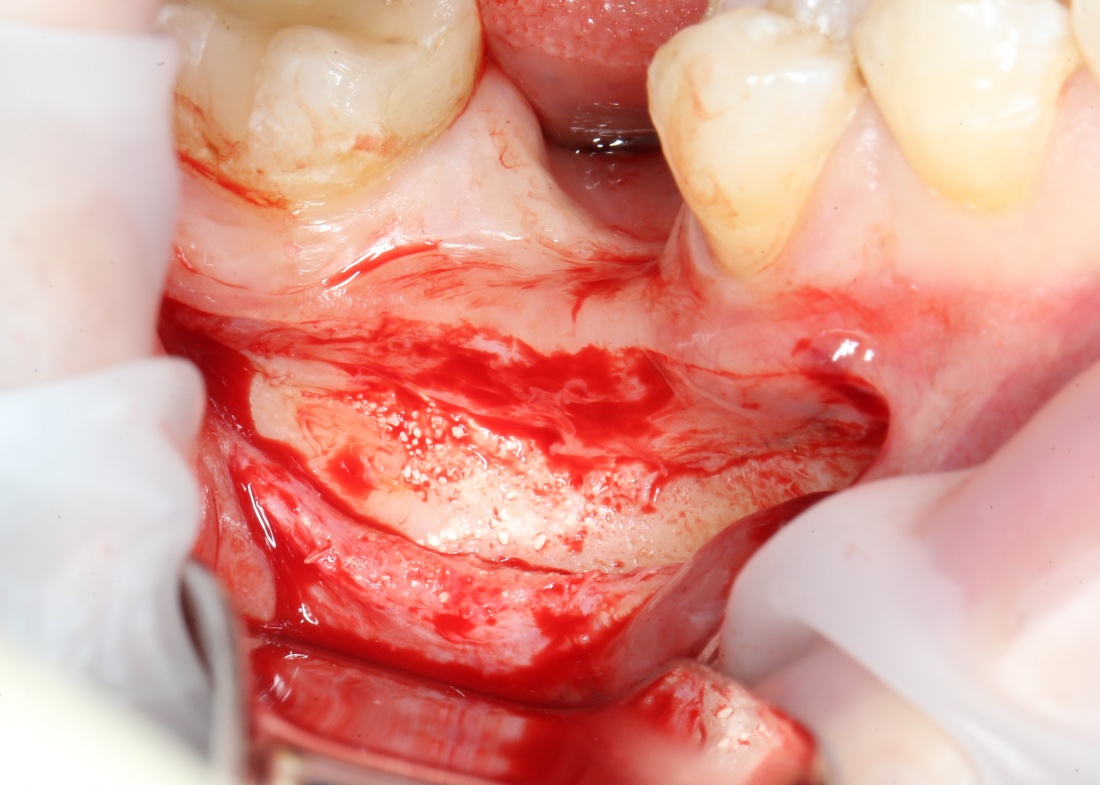

3. Скелетирование альвеолярного гребня.

В отличие от других видов остеопластики, не проводится. Напомню, что для перемещаемого фрагмента, периост является единственным источником питания, и было крайне безответственно лишать кость этого источника. Кроме того, периост частично удерживает перемещаемый фрагмент на месте, не давая ему совсем уж отвалиться.

Максимум, выделите себе полоску шириной в 3-4 миллиметра для работы инструментом и фиксации винтов. Этого будет достаточно.